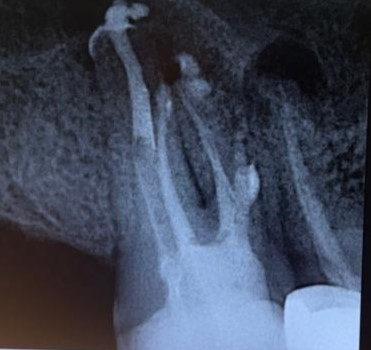

4. Radiographic Examination

- Periapical X-ray of Tooth #17

- Panoramic X-ray

5. Diagnosis

- Chronic Periapical Abscess (Tooth #17)

- Failed Previous Root Canal Treatment

- Missed Buccodistal (BD) Canal

- Missed Mesio-Buccal 2 (MB2) Canal

B. Obturation

- Root canal obturation performed using Total Fill (BC) Sealer (FKG)and Denco Cuttapercha Points.

- A small perforation (identified during retreatment) was sealed with Mineral Trioxide Aggregate (MTA) under microscopic visualization.